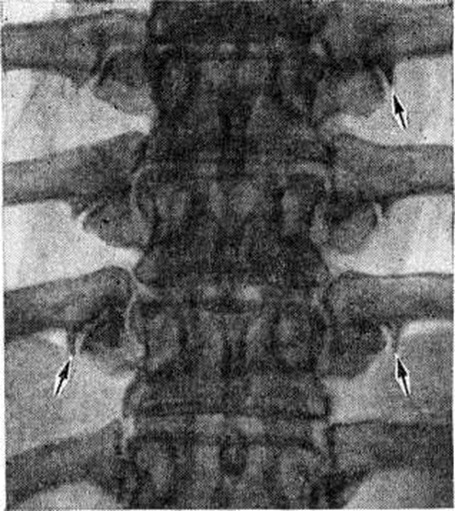

Диагноз Спондилоартроз ставят главным образом на основании клиники и данных рентгенологического исследования. На рентгенограммах определяется сужение суставных щелей, субхондральный остеосклероз (смотри полный свод знаний), краевые костные разрастания (рисунок), продолжающие суставные поверхности, удлинение и деформация суставных отростков.

Рис

Спондилоартроз рентгенограмма грудного отдела позвоночника (прямая проекция) при спондилоартрозе: стрелками указаны шиповидные костные разрастания по краям суставных поверхностей реберно-поперечных суставов.